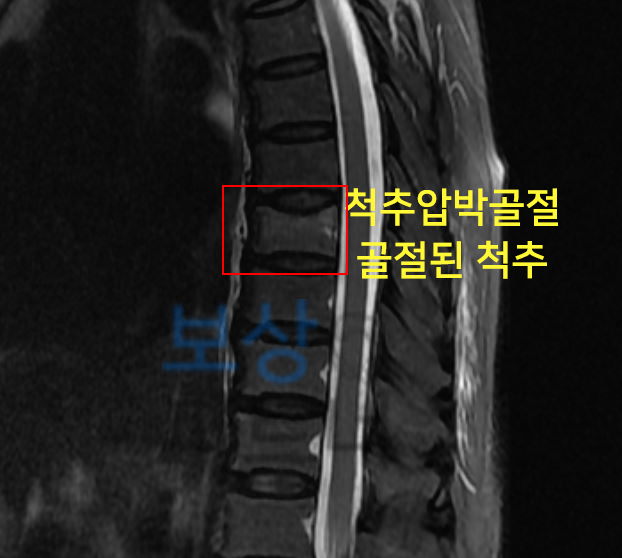

수술한지 얼마 되지 않았어도 골절로 인해 금속고정술을 할 정도면 장해 보상까지 알아보셔야 하고, 의료용 워커 허리 고관절 골절 인공관절 치환술 장해 특히 허리 골절은 비수술 보존적 치료를 시행하셨어도 후유장해 보상 가능성 있습니다.

요추1번 골절 보존치료 진행하신 윤@@님

후유장해 보험금 3,900만 원

흉추12번 압박골절 보존치료 진행하신 조@@님은

후유장해 보험금 2,800만 원

지급받으셨습니다.